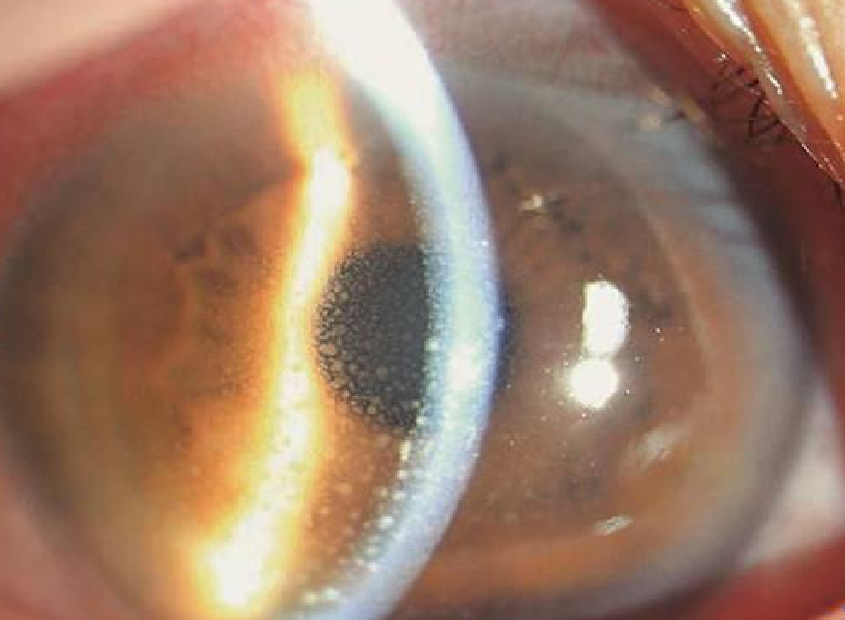

通过一系列详细检查,岳阳爱尔眼科医院角膜及眼表专科汪洁主任初步诊断赵女士为“左眼单纯疱疹病毒性角膜炎”。汪主任介绍说,病毒性角膜炎指的是受病毒致病原感染角膜而引起的炎症,常见的症状有:畏光、流泪、酸痛、视力模糊等。 作为秋冬常见眼病,病毒性角膜炎病程长,且易反复发作,多次发作后使角膜混浊逐渐加重,可导致角膜瘢痕形成、新生血管化、穿孔等,是临床上较为常见的致盲眼病之一。

根据病变累及深度分为三型:

上皮型(点状、树枝状、地图状角膜炎)

基质型(浅中基质型、深基层型角膜炎)

内皮型(线状、弥漫型内皮炎)